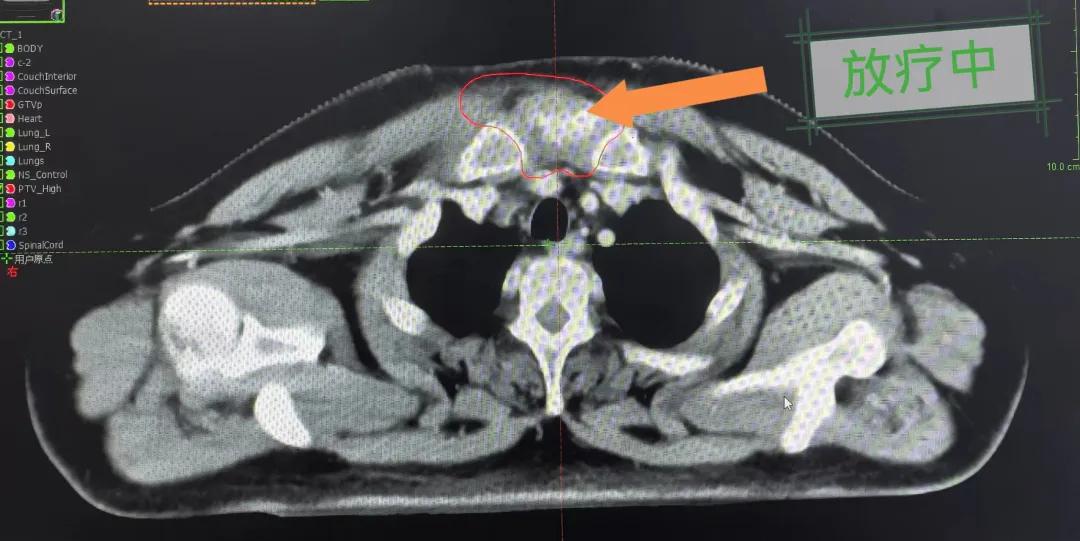

隨后,趙亮主任帶領(lǐng)放療團(tuán)隊(duì)以最快的速度完成了患者的放射治療計(jì)劃,在保證放療精準(zhǔn)打擊腫瘤的同時,利用先進(jìn)的三維立體精確放療技術(shù),最大限度的避免心臟、肺部的損傷發(fā)生,整體治療精準(zhǔn)度達(dá)到1mm以內(nèi)。經(jīng)過10次的放射治療后,患者疼痛已明顯減輕,胸部腫物肉眼可見的縮小,患者及家屬臉上終于露出久違的笑臉。

治療期間,患者沒有出現(xiàn)明顯不適,治療結(jié)束后,患者胸壁腫物由最初8cm縮小至約1cm,后患者至外科行手術(shù)治療。